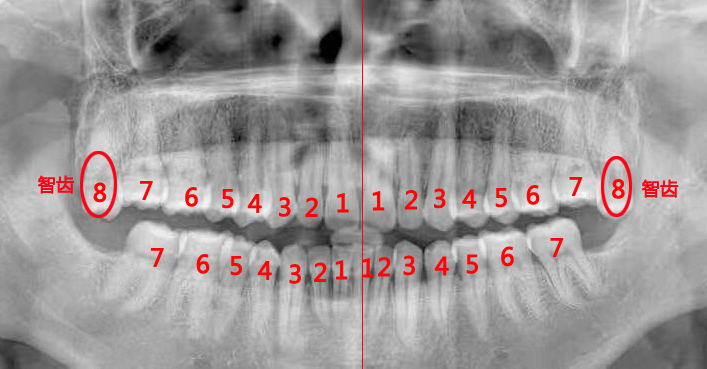

最准确的方法:拍片检查,借助X光让智齿现形。

说明:检查智齿或拔智齿前,医生一般都会建议拍个全景片,很多人觉得麻烦,其实这是非常有必要的。全景片可以清晰地呈现上下颌骨、全口牙列的全貌,以及智齿与邻牙、周围牙槽骨的关系,帮助医生评估拔牙的难度,并安全快速地拔除智齿。拍片时,需要穿防护服。

这种情况如果平时没有明显症状,一般要拍片才能发现,如下图:

如果上面长了、下面没长,或者下面长了、上面没长,那长出来的那颗就会更加放肆地过度萌出。这样一来,第二磨牙会被挤得更惨,对侧的牙龈和口腔黏膜也会跟着遭殃。如下图: